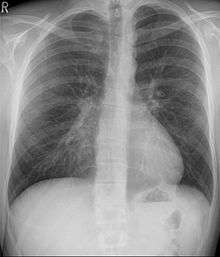

Pectus excavatum is initially suspected from visual examination of the anterior chest. Auscultation of the chest can reveal displaced heart beat and valve prolapse. There can be a heart murmur occurring during systole caused by proximity between the sternum and the pulmonary artery.[17] Lung sounds are usually clear yet diminished due to decreased base lung capacity.[18]

Many scales have been developed to determine the degree of deformity in the chest wall. Most of these are variants on the distance between the sternum and the spine. One such index is the Backer ratio which grades severity of deformity based on the ratio between the diameter of the vertebral body nearest to xiphosternal junction and the distance between the xiphosternal junction and the nearest vertebral body.[19] More recently the Haller index has been used based on CT scan measurements. An index over 3.25 is often defined as severe.[20] The Haller index is the ratio between the horizontal distance of the inside of the ribcage and the shortest distance between the vertebrae and sternum.[21]

Chest x-rays are also useful in the diagnosis. The chest x-ray in pectus excavatum can show an opacity in the right lung area that can be mistaken for an infiltrate (such as that seen with pneumonia).[22] Some studies also suggest that the Haller index can be calculated based on chest x-ray as opposed to CT scanning in individuals who have no limitation in their function.[23]